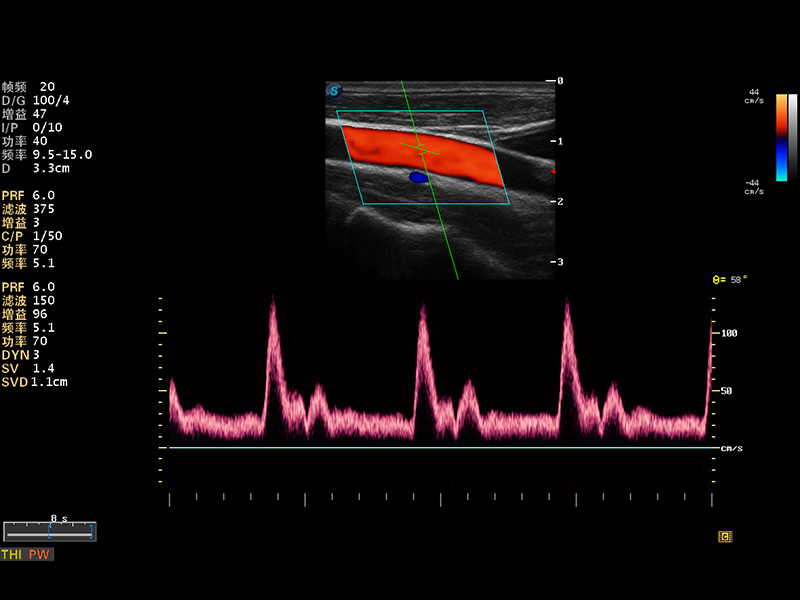

S8 EXP便携式彩色多普勒超声诊断仪是银河优越会研发的高端全身应用型便携彩超。高通道的VIS平台融合可视化(Visual)、智能化(Intelligent)和人性化(Smart)的特点,配以银河优越会自主研发生产的探头大家族,使您能够快速、准确的获得病人信息,提高工作效率的同时减轻疲劳。

成像技术

多波束形成器

μ-Scan微米成像

谐波成像